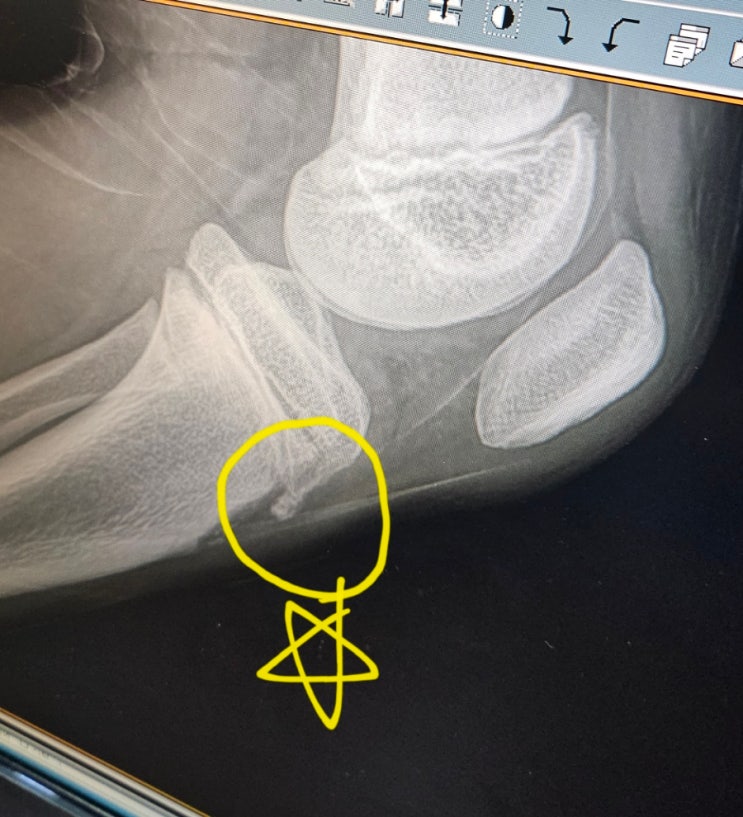

오스굿_슐레터병_청소년기무릎통증_성장통인줄알았던 오스굿_정형외과방문기

일주일전부터 초등학교6학년 둘째가 왼쪽 무릎이 아프다고 했다. 처음엔 넘어졌는지.. 어디 부딪힌건 아닌...